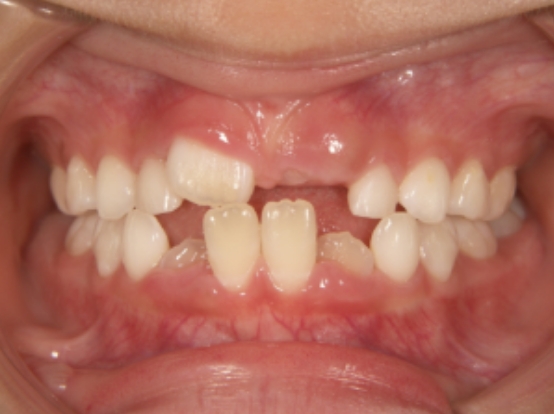

治療中➁ 小1:7y5m 装置使用後1か月で受け口が改善